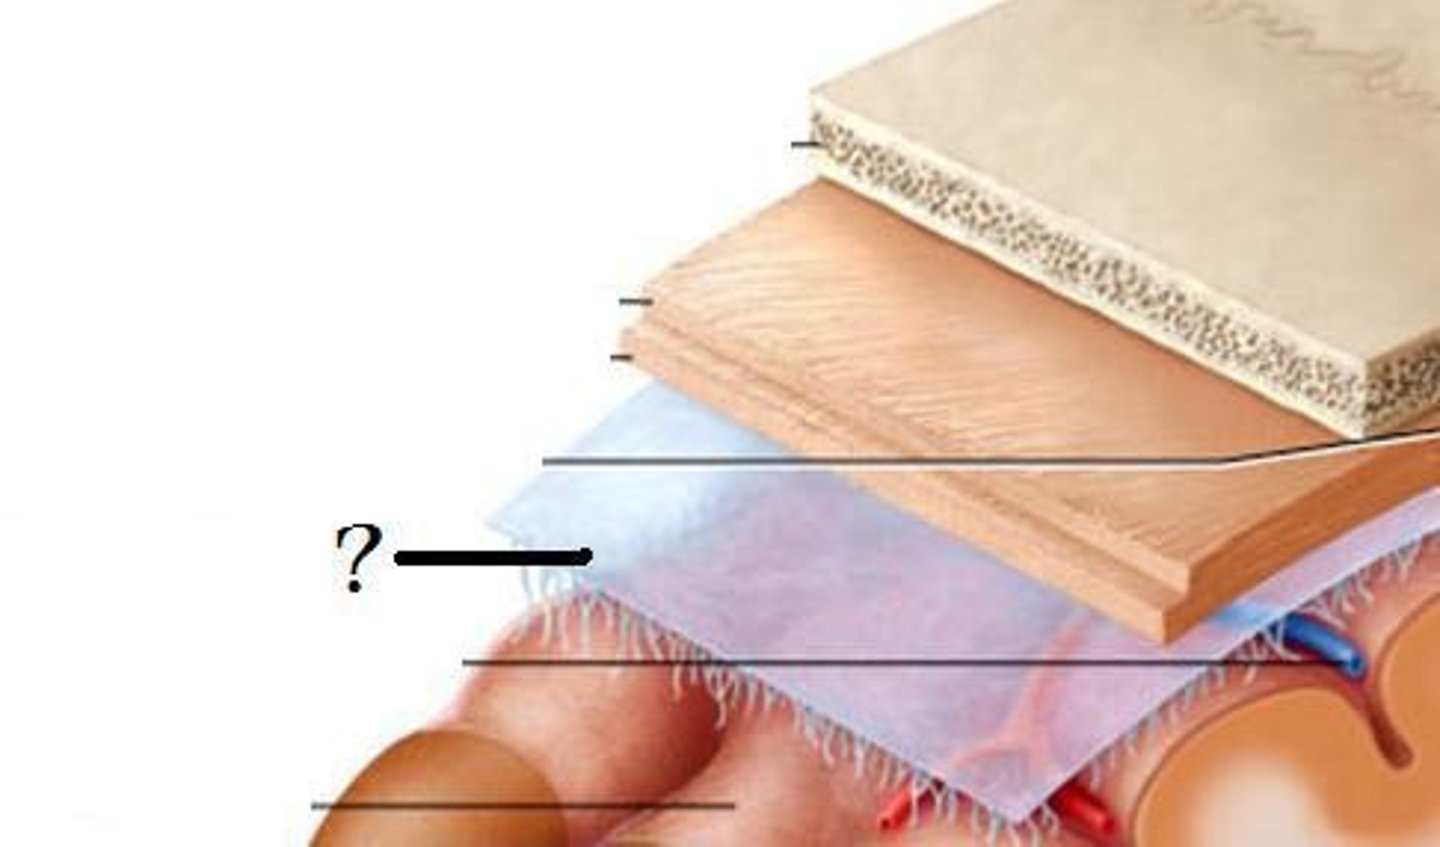

Meninges

-Three connective tissue membranes that envelope the CNS

-Protect the CNS and provide structural framework for its arteries and veins

Meninges Location

-Lies between the nervous tissue and bone

Arachnoid mater

-Transparent membrane over brain surface

Subarachnoid space

-Separates arachnoid mater from pia mater below

Subdural space

-Separates arachnoid from dura mater above in some spaces

Pia mater

-Very thin membrane that follows contours of brain, even dipping into sulci

-Not usually visible without a microscope